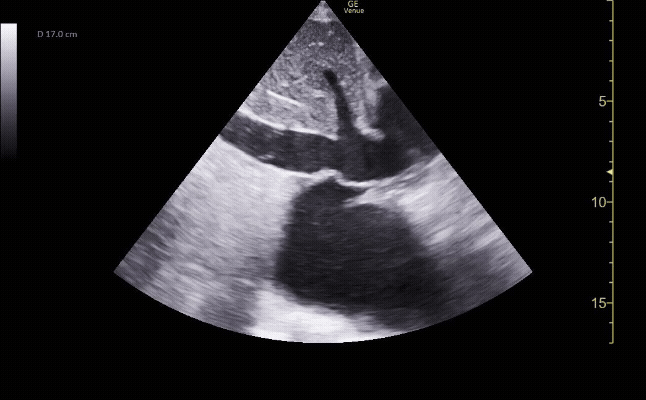

Parasternal long view showing the right ventricle, left ventricle, left atrium mitral valve, aortic root, and descending aorta.

c/o Kyle Ackerman, MD